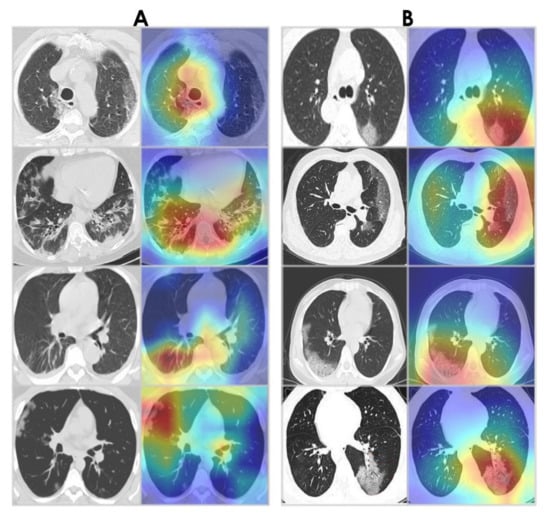

4.5. Grad-CAM Visualizations

Grad-CAM algorithm [67] was used to examine the behavior of the WAE network by visualizing the areas of infection in our chest CT images. This provides insight into what the network has learned and what part of its input contributed to detecting COVID-19. Grad-CAM visualizations for WAE are shown in Figure 19. Note that the WAE’s area of interest at the time of prediction is represented by the red and green visuals. It is noticed that the activations maps are focused on the lungs. Interestingly, in the majority of cases, WAE was able to localize the disease region based on relevant features from the chest CT images for both datasets.

Figure 19. Grad-CAM visualizations. (A) Sample CT images from the SARS-CoV-2 CT-scan dataset [42]. (B) Sample CT images from the COVID-CT dataset [22].